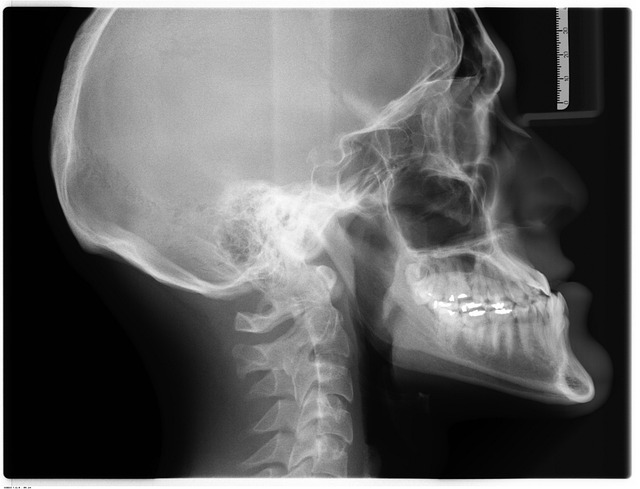

Equipamentos e Exames Convencionais

Abrange equipamentos radiológicos, radiografia, processamento, anatomia radiológica (2 partes) e exames radiológicos.

Foco em operação de máquinas, posicionamentos e interpretação básica de imagens para diagnósticos precisos.